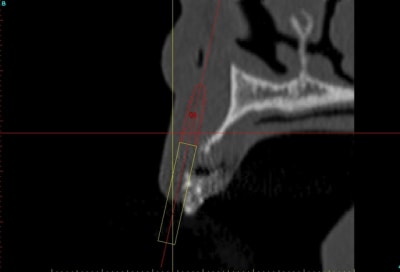

J'aurais bien aimé avoir des coupes radio avant/après.

C'est possible?

voilà, j'ai trouvé 5 mn...

le projet simplant est théorique, ça ne correspond pas à ce qui sera posé, c'était pour étude.

Il n'y avait pas grand chose en effet.